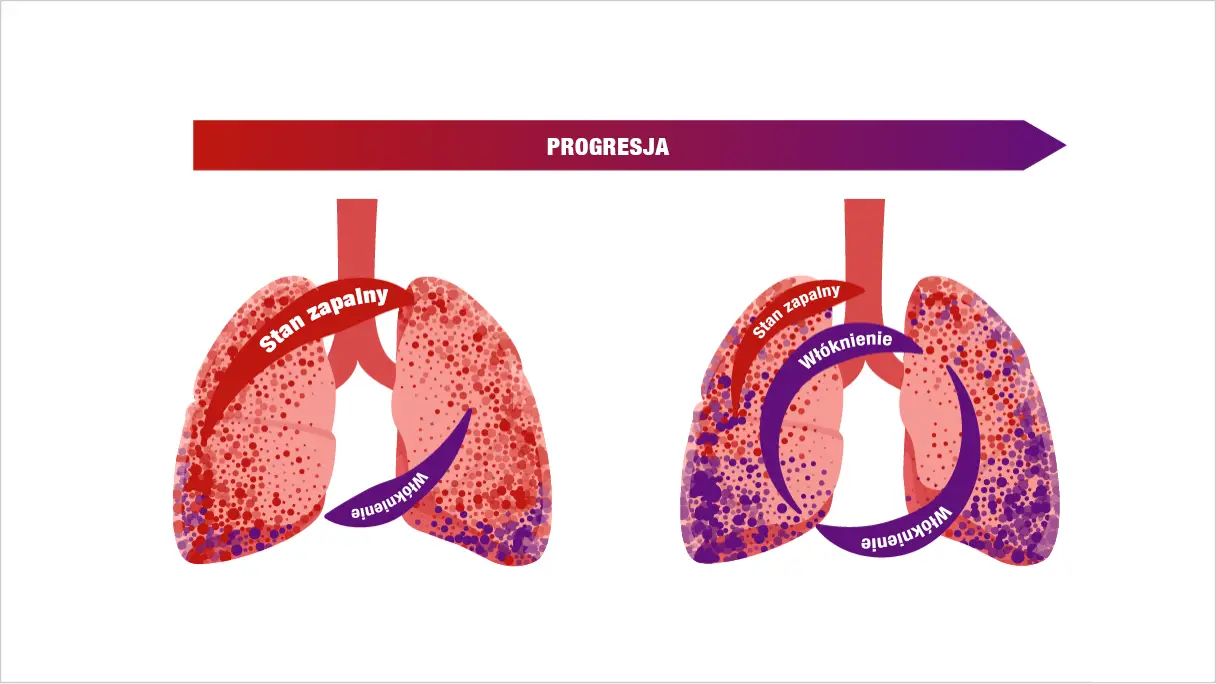

PATOGENEZA PID-BTC IMPLICĂ INTERACȚIUNEA PRECOCE ÎN EVOLUȚIA BOLII DINTRE INFLAMAȚIE ȘI FIBROZĂ5-7

O interacțiune complexă a proceselor inflamatorii, fibrotice și vasculare duce la activarea și proliferarea fibroblastelor, diferențierea lor în miofibroblaste și secreția excesivă a matricei extracelulare5,6,10

PID-BTC POT ÎMPĂRTĂȘI MECANISME DE AUTO-ÎNTREȚINERE ALE FIBROZEI PULMONARE PROGRESIVE4,10

Indiferent de diagnosticul clinic, există aspecte comune în mecanismul patogen care stau la baza care conduce un proces auto-întreținut de fibroză pulmonară4

Odată ce fibroza pulmonară devine un proces auto-întreținut, fibroblastele pot deveni parțial independente de stimularea externă și de răspunsul inflamator inițial11,12